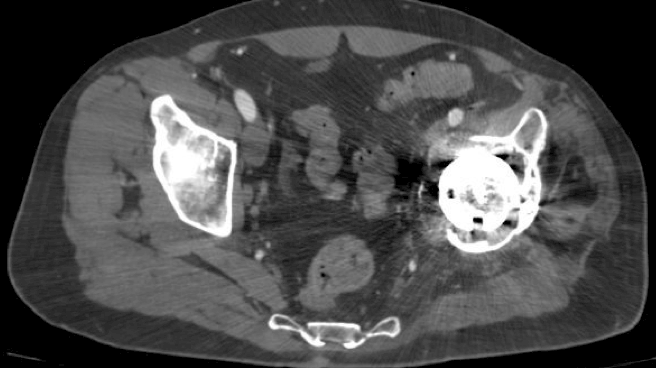

Preoperative: 3D Proposal